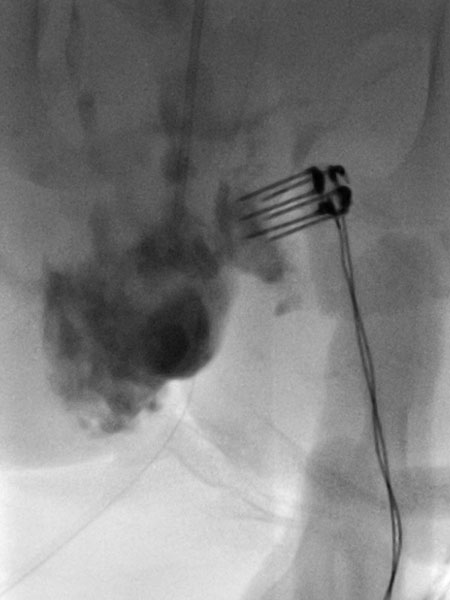

After confirmation of the diagnosis, bleomycin electrosclerotherapy was performed. For this purpose, the venous malformation was first punctured on both sides with a needle under ultrasound guidance and injected with contrast medium. Good needle placement, no major drainage veins were found.

A total of 0.75 mg bleomycin (diluted one to three in contrast medium) was now injected directly into the venous malformation via the two horizontal needles. Subsequently, a total of 11 applications of reversible electroporation with finger electrode with 15 mm active needle length were performed on both sides.